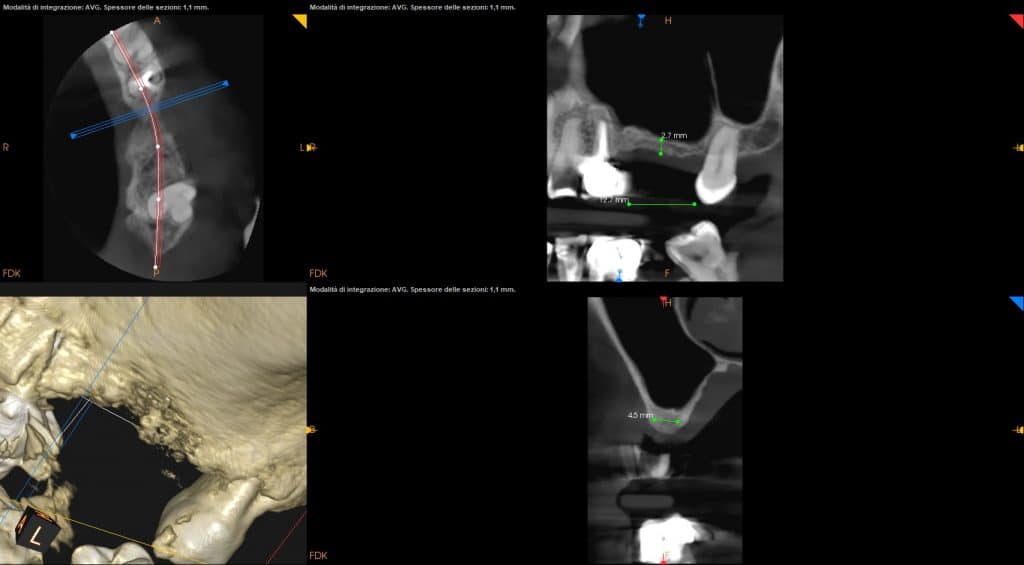

- CBCT helps us for the exact position of the window

- CBCT should guide the detachment of the sinus membrane

- Attention should be paid to any bone septa highlighted by the CT scan

- Two implants are placed drilling the 3 mm of residual crestal bone

CBCT